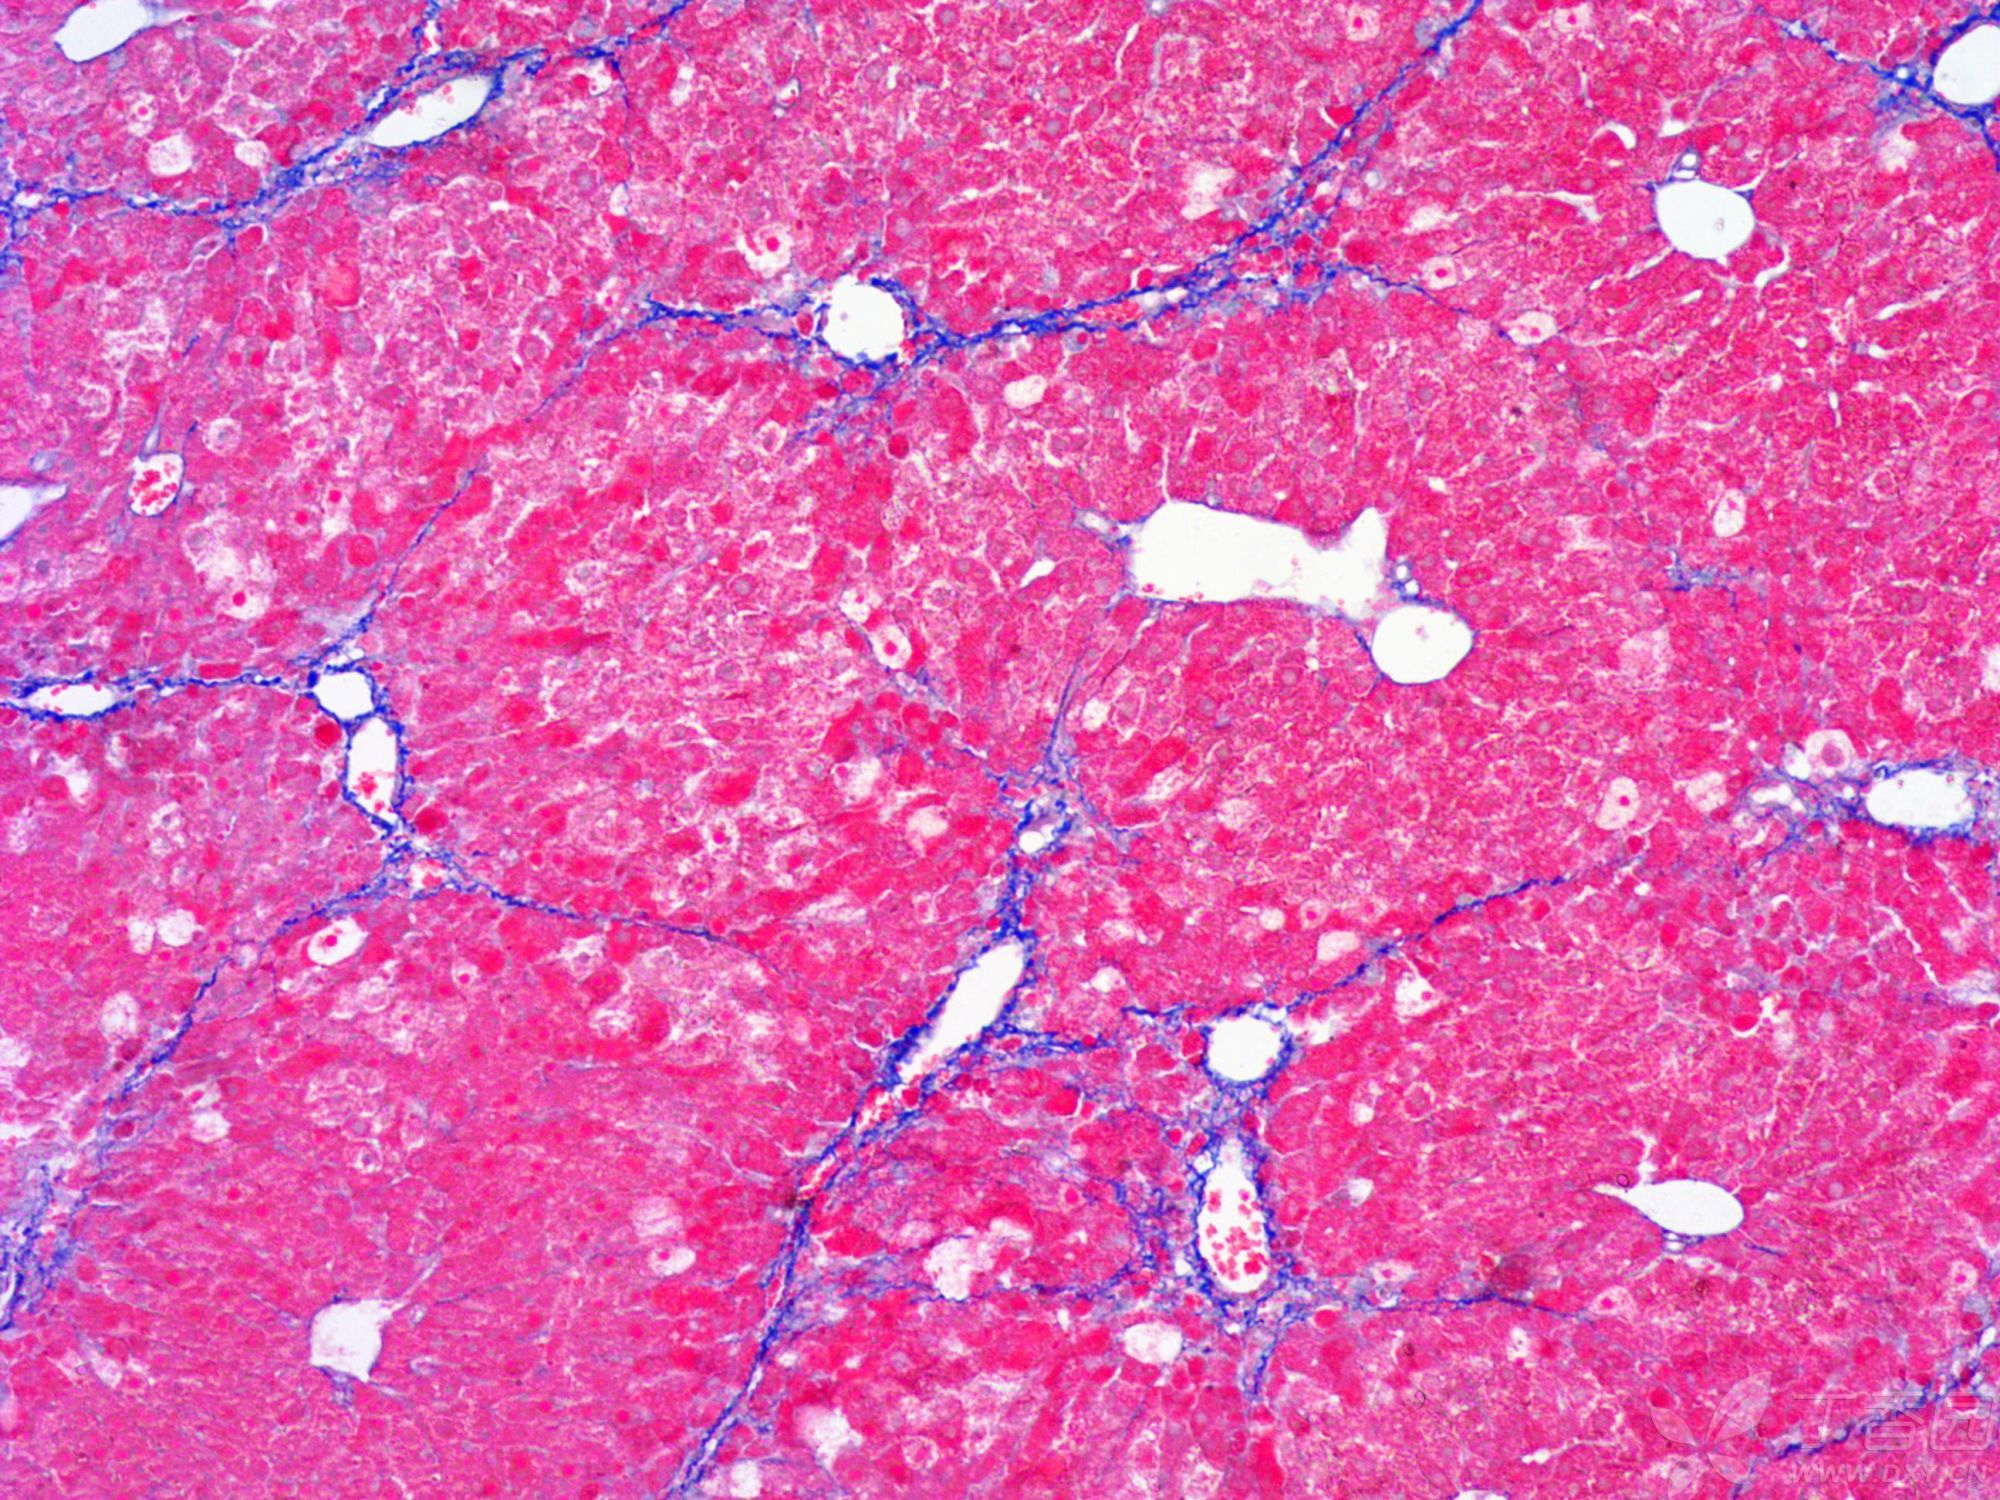

小鼠纖維化